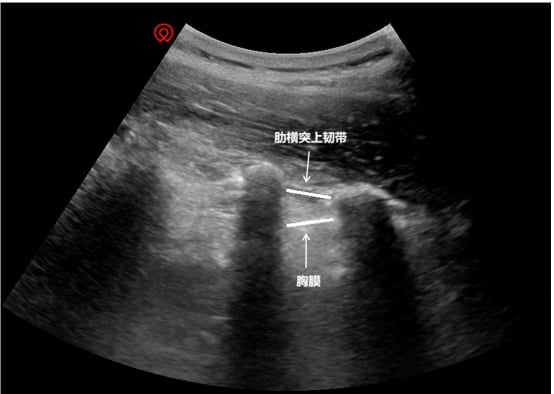

2. 精准手术:超声与 C 臂的双重守护